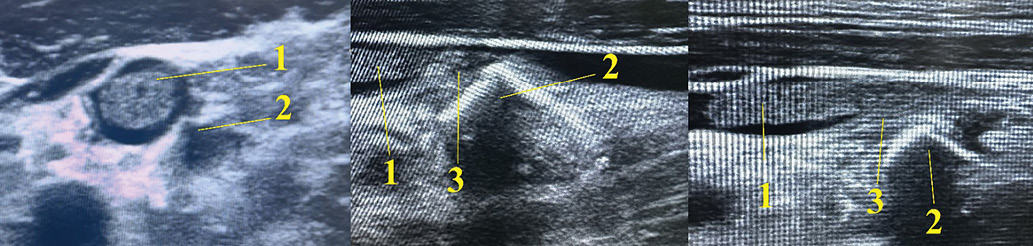

According to ultrasonography (USG), the fragment was located between the left common carotid artery and the internal jugular vein (IJV), penetrating the IJV. A 3 cm floating thrombus attached to the fragment was visualized within the IJV lumen (Fig. 3).

Images obtained by the authors

Fig. 3. Left neck ultrasound: 1 — floating thrombus in the lumen of the internal jugular vein; 2 — metallic foreign body (fragment) penetrating the lumen of the internal jugular vein; 3 — site of attachment of the floating thrombus to the metallic foreign body (fragment)